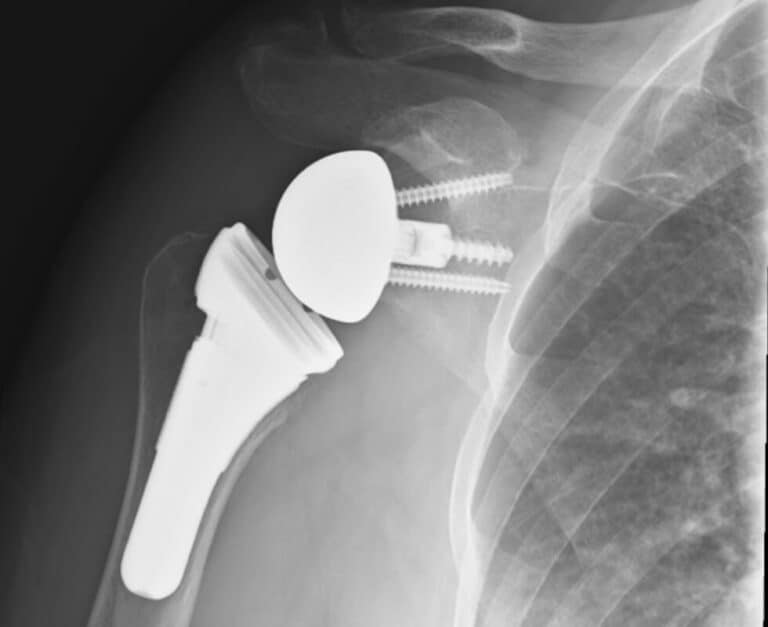

DePuy, Delta